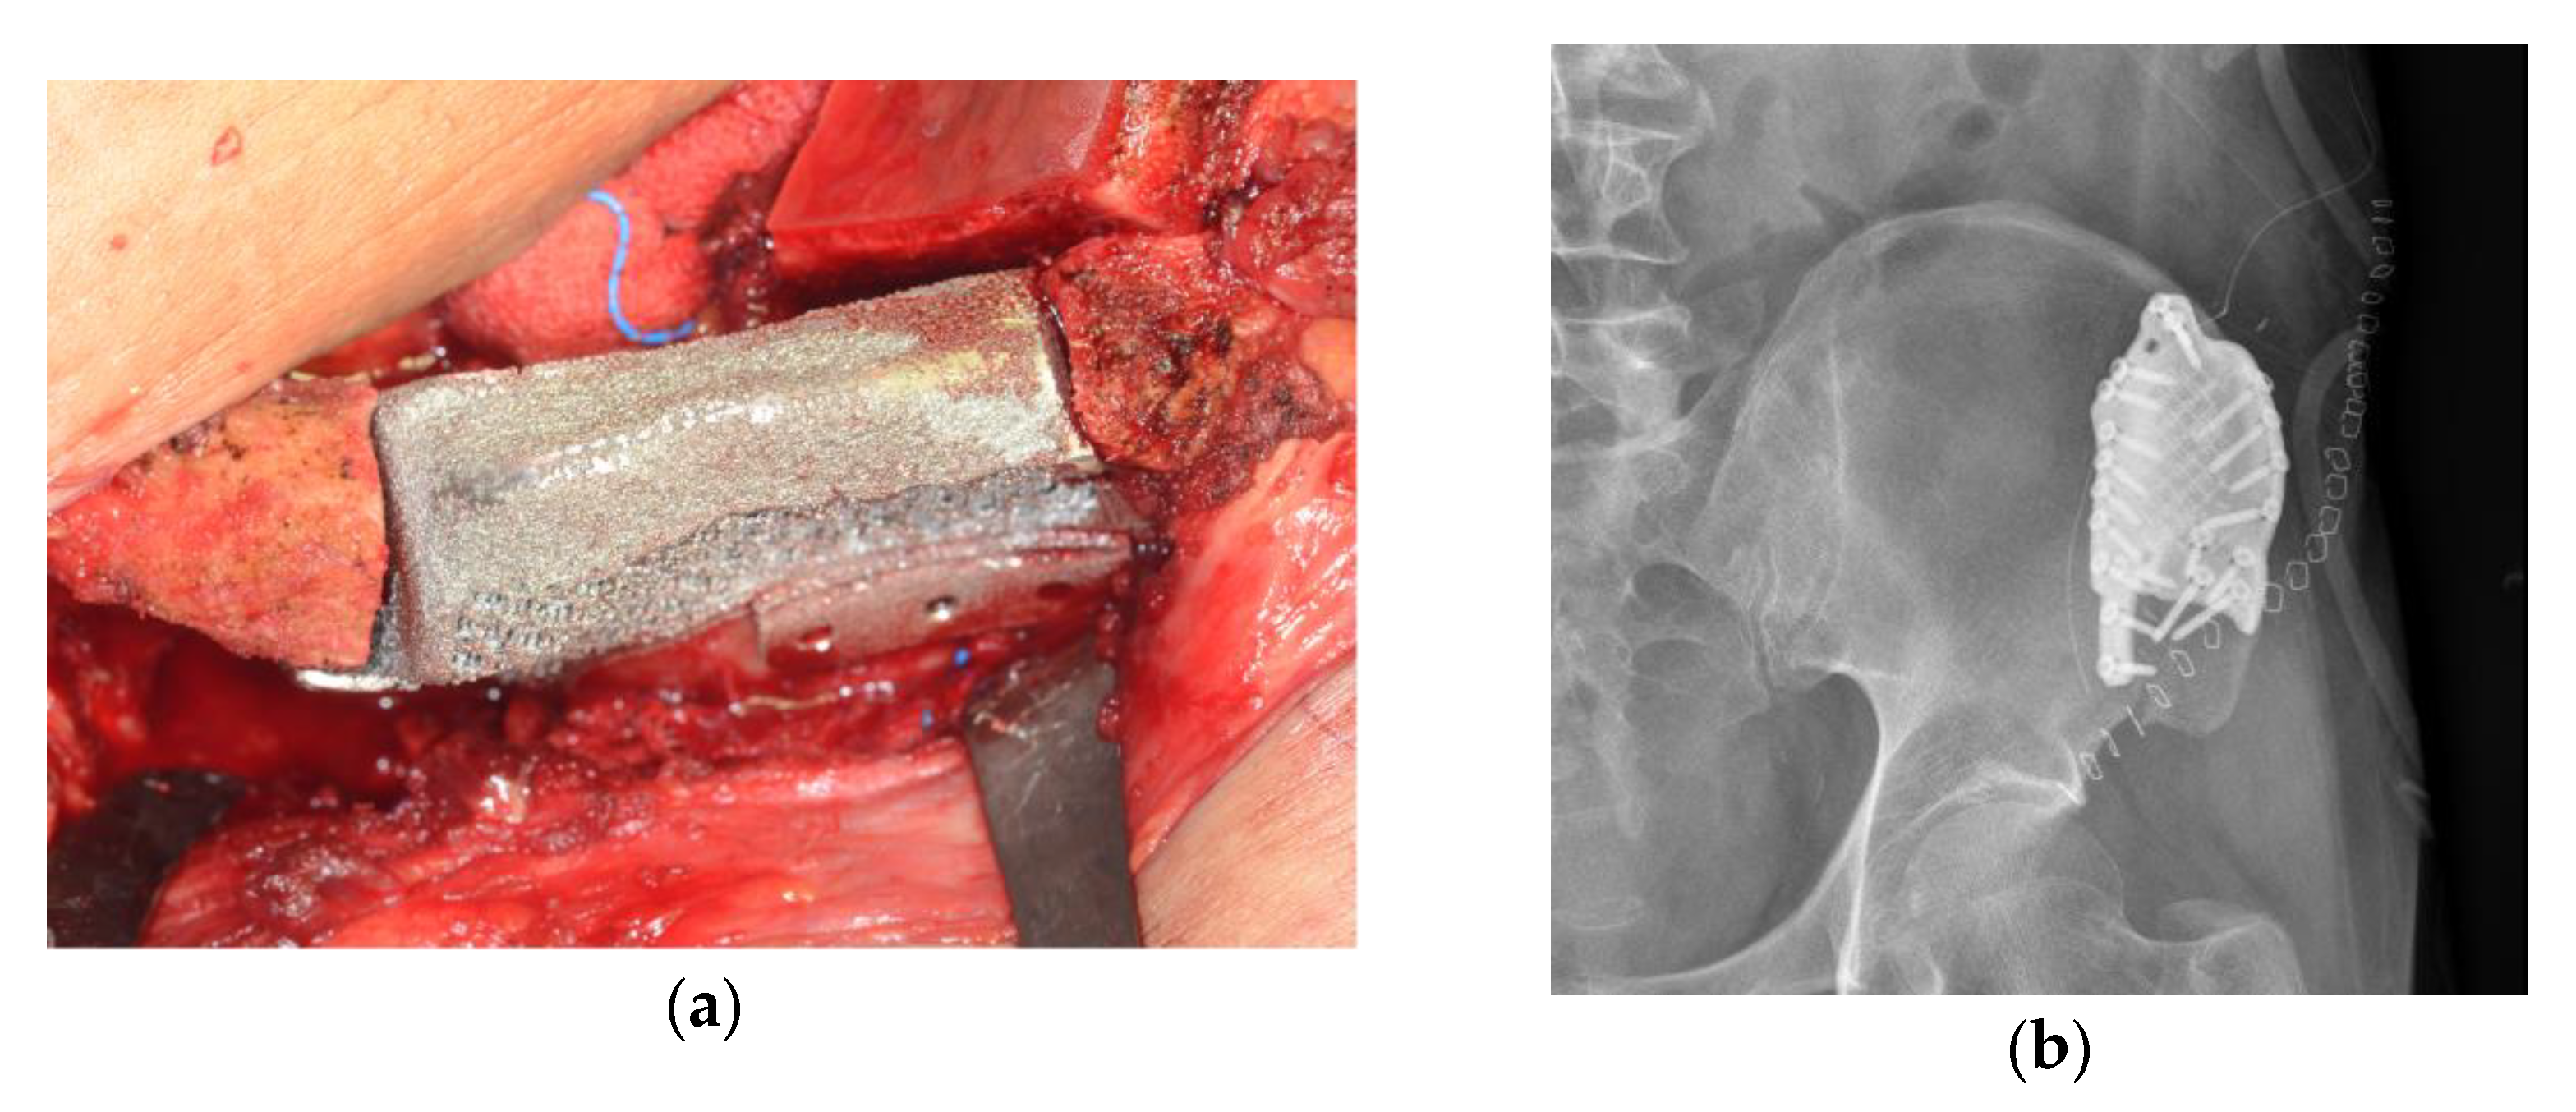

Open reduction of the fractured iliac crest bone was performed by applying a 3D-printed titanium implant to the external surface. A preformed 3D-printed porous titanium implant was inserted into the bone defect of the fractured iliac bone. The titanium implant was fixed to the iliac bone with 2.4 mm diameter screws through the pre-designed hole (Figure 3).

Figure 3.

(a) Intraoperative photograph; open reduction using customized titanium implant. (b) Postoperative iliac AP X-ray.

From 2 weeks postoperatively, the patient was able to stand and walk and was able to live without any discomfort for up to 1 year postoperatively. There was no recurrence of the primary tumor and no other complications were observed (Figure 4).

Figure 4.

Postoperative radiograph: (a) patient-specific implant shown on left iliac bone after 3 months; (b) well-reconstructed mandible after 4 months.